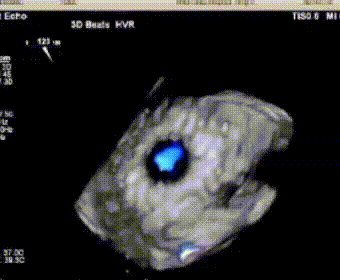

术前经食道超声评估